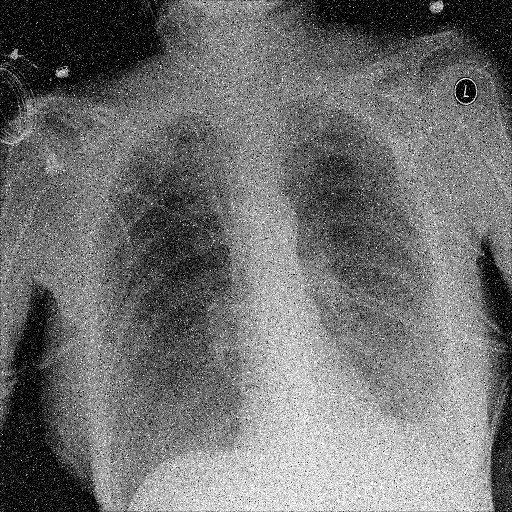

In Fig. 1, we show four ϵitalic-ϵ\epsilon-LDP-processed CXR images of clinical cases obtained with the image domain LDP, which directly imposes the Laplace mechanism on the input image, with different privacy budgets together with the original images. Fig. 2 shows four ϵitalic-ϵ\epsilon-LDP-processed CXR images of clinical cases obtained with DP-GLOW and different privacy budgets together with the original images. In case 1 for DP-GLOW, there is decreased permeability in the bilateral hilar regions. Although this hilar opacity tends to be preserved with a larger privacy budget, the entire image is degraded when the privacy budget becomes 101HWsuperscript101𝐻𝑊10^{1}\cdot H\cdot W. A similar tendency is observed in the images of all the four cases for DP-GLOW; for example, in case 4 with ϵ=101HWitalic-ϵsuperscript101𝐻𝑊\epsilon=10^{1}\cdot H\cdot W, the lung opacity suggesting pneumonia in the right lower lung field is well preserved, while the entire image is degraded.